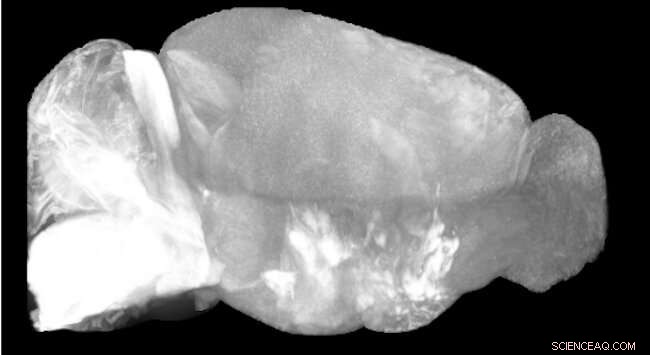

Credit: University of Glasgow

With RAPID, the researchers propose a new auto-focusing technology compatible with light-sheet microscopy that is capable of automatically correcting the misalignments introduced by the sample itself in real time. In cubic centimeter-sized, cleared samples, such as intact mouse brains, the autofocussing removes image degradation to enable enhanced quantitative analyses.

The new method is inspired by the optical autofocus systems found in reflex cameras, where a set of prisms and lenses transforms the blur of the image into a lateral movement. This allows the alignment of the microscope to be stabilized in real time, producing sharper, more richly-detailed images.